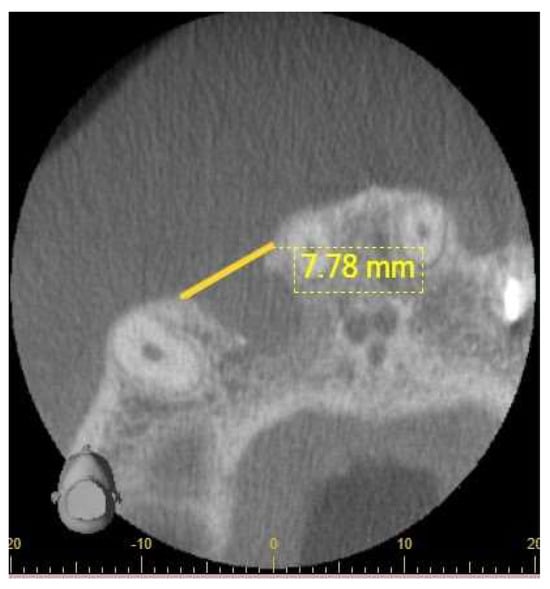

2.3.2. Cone-Beam Computer Tomography (CBCT) Radiographic Examination and Evaluation